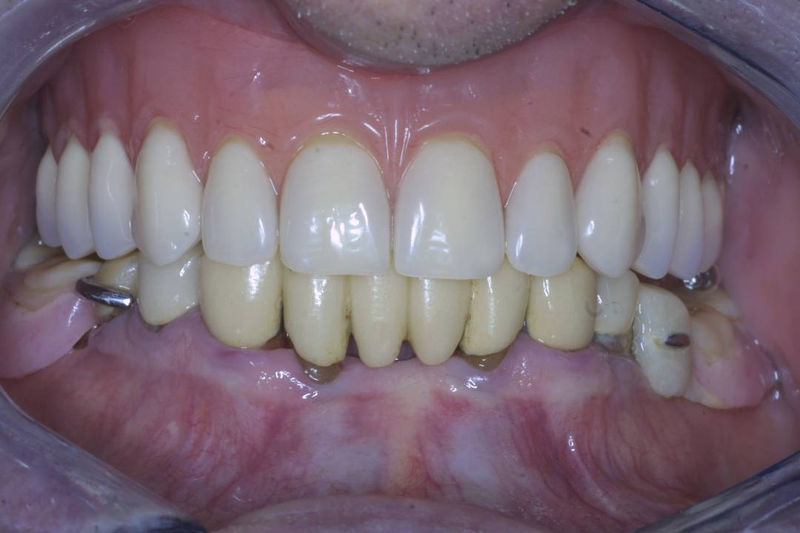

Implantes, ortodoncia y coronas.